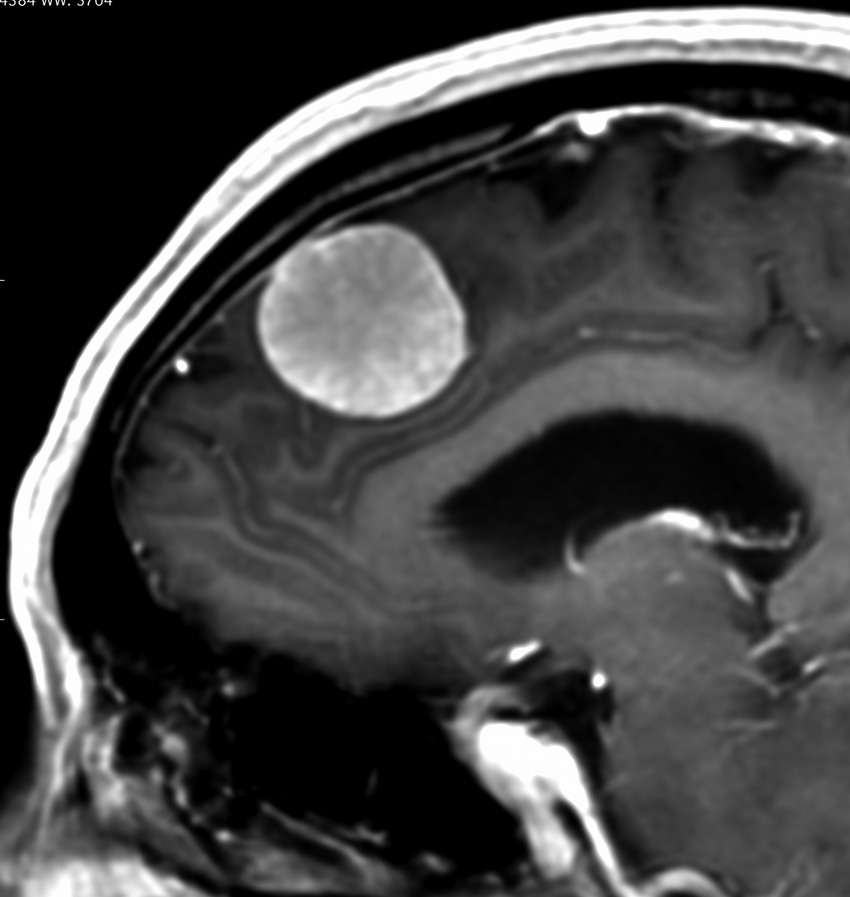

左は,造影剤を使ったガドリニウム増強MRIです。腫瘍が白く丸く見えます。右はフレア画像で,腫瘍の周囲の脳浮腫(脳のはれ)です。左前頭葉が,かなり強くはれています。この腫瘍は小さいのですが,脳のはれが強すぎるので手術摘出したほうがいいです。浮腫が悪化すると,てんかん発作や認知機能低下がでる可能性があります。

典型的な髄膜腫

この髄膜腫は中程度の大きさのものです。円蓋部髄膜種という最も多い最も手術の簡単なタイプです。麻痺や失語症やてんかんなどの症状はありません。とても美しくて若い女性の髄膜腫でしたが,子供に遺伝はしませんし,癌などと違ってタバコなどこれといった原因がなくて発生するものです。

MRIでの髄膜腫の見え方は撮影の仕方によっていろいろです。左からT1強調画像,T2強調画像,フレア画像といいます。腫瘍の横に小さく白い領域がありますが,これは脳の腫れた部分で脳浮腫といいます。髄膜腫があると周囲に脳浮腫が生じることがあります。

最も見やすいのが,ガドリニウム造影剤を注射して撮影するものです。一般的に髄膜腫は造影剤で白く映し出されます。この腫瘍は左脳側にあります。MRIの軸面という輪切りの写真では左右が逆になりますから注意してください。脳を下から見た図になっています。MRIはいろいろな方向から腫瘍を見ることができますが,右は冠状断という正面から見た図です。よく見ると腫瘍の上と下のはじっこに線状に糸を引いたように造影される部分があります。これをテールサイン(しっぽのサイン)といいます。腫瘍が硬膜に沿って延びている可能性があることを示しています。